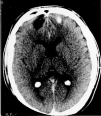

Fig. 1. Tomografía computarizada craneal.